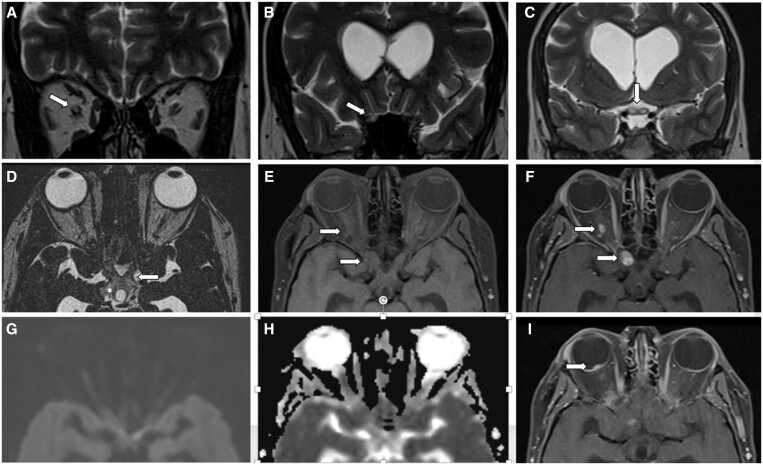

Optic nerve haemangioblastoma (ONH) is an uncommon, benign, non-meningothelial, mesenchymal tumour of unclear origin. Most are associated with von Hippel-Lindau (VHL) syndrome (71%), and only 40 cases have been reported in the medical literature. Most of the patients develop non-specific visual symptoms, including decreased visual acuity and/or loss of visual fields, exophthalmos, trigeminal neuralgia, and retroorbital pain. Optic nerve sheath meningioma and optic nerve glioma are among the differential diagnoses that may be considered in this location. Contrast-enhanced MRI is considered an optimal diagnostic tool, which helps to determine some characteristics that guide towards an adequate diagnosis and treatment. We present a 42-year-old patient with a history of VHL syndrome in whom a cerebellar lesion and optic nerve lesions were evidenced, and we did a review of the literature and case analysis.